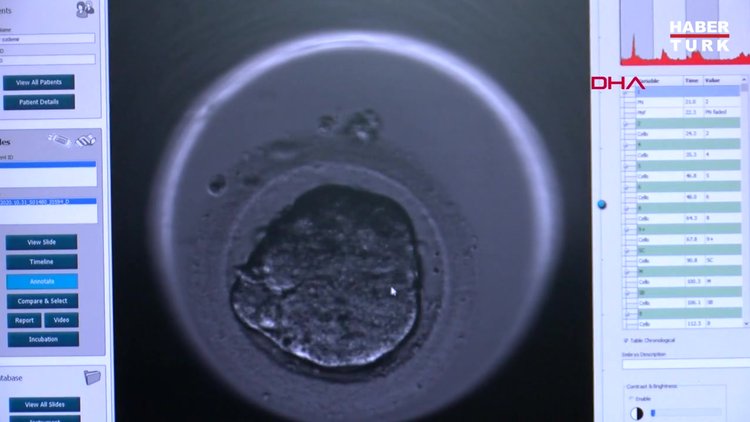

Uzmanlar, kısırlığın tüm dünyada birçok hastalık ve nedenle yaklaşık 60-80 milyon çifti etkileyen bir sağlık sorunu olduğunu belirtiyor.